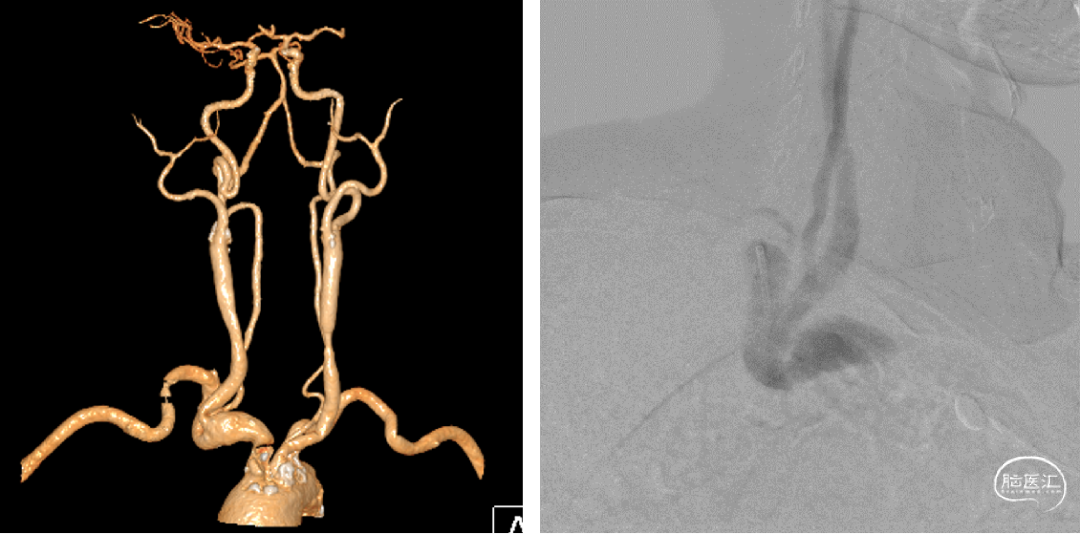

头臂干直径13mm,无相应的球扩式支架,且球扩过程中容易挤碎血栓,因此考虑自封式支架更合适。

编制支架近端定位困难,编制支架自膨后长度难以把控。因此选用支架选用开环,网孔相对较密的9×30 Precise颈动脉支架。

术后三日复查CTA如下,复查CT可见支架位置及形态良好,支架内及远端血流良好。

术后三天CTA